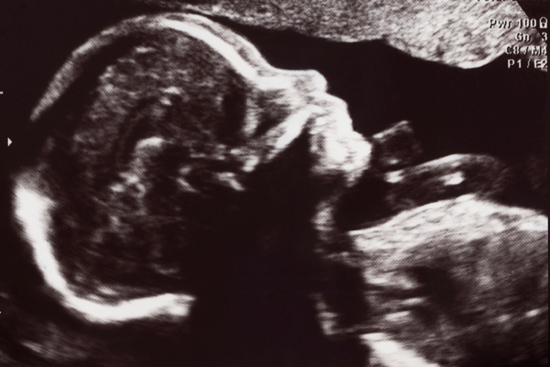

Research by Martha Werler, an SPH professor and chair of epidemiology, finds that women who had a child with neural tube defects were twice as likely to have used opioids early in their pregnancies as mothers whose children were born healthy. Photo courtesy of the School of Public Health